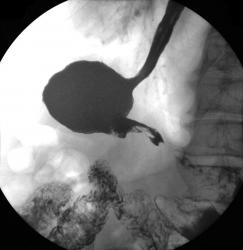

Осмелюсь предположить что в антральном отделе желудка есть рак,  инфильтративная форма.

На серии представленных вами снимков сделанных во время скопии, отмечается регидность участка и утолщение слизистой(отмечено стрелками), жалко только  что не была выведена петля 12п.к. в положении стоя, там бы мы увидели четко антральный отдел:

Да это один и тот же больной.Гистологическая верификация-аденокарцинома.И в кишке и в пищеводе дивертикулы.

В антарльном отделе  не толко ригидность ,а стойкое циркулярное сужение.А вот по большой кривизне можно сказать ,что ригидность, хотя контур стенки ровный четкий, но при двойном контрастировании толком не расправился, да и перистальтика почти отсутствует

Случай интересный, в плане сочетания дивертикула пищевода и тонкого кишечника с органикой желудка.

Протяженность процесса, учитывая зазубренность большой кривизны, надо думать была значительная?

Надо думать, что в антральном отделе, по большой кривизне, имела место быть "чашеподобная" карцинома, со значительным изъязвлением?